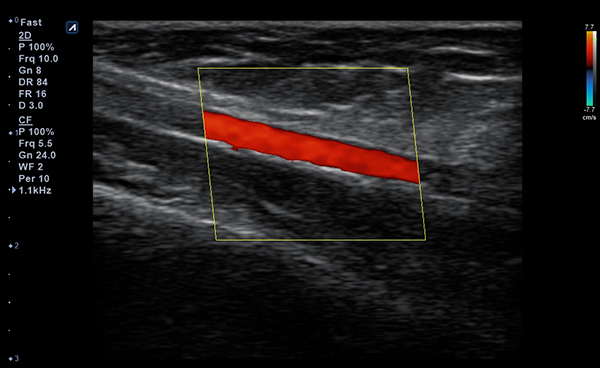

Alpinion Medical Systems, la empresa de sistemas de ultrasonido, ha combinado tecnologías

de procesamiento de imágenes y transductores para garantizar que minisono proporcione

imágenes 2D de alta definición e información de Doppler más claras y nítidas.

minisono ofrece funciones esenciales con el nivel de rendimiento necesario

para garantizar que los exámenes y diagnósticos sean precisos.

- Imaging modesB-mode, CF, M, PW, PD

- Frequency3-12 MHz